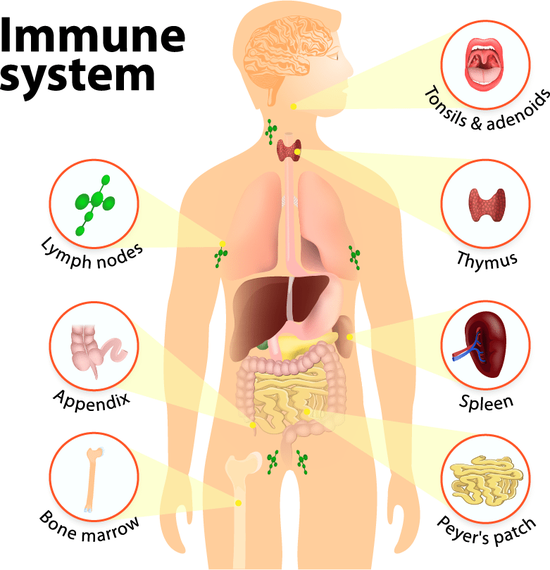

04 身体有慢性炎症的人

有时我们会感到大脑反应迟缓,就像有团迷雾在脑子里,想事情想不清楚,这可能是身体低水平的炎性反应造成的。

在一个研究中,科学家给 20 个参与实验的人注射了低浓度的伤寒沙门氏菌疫苗,这个疫苗会导致微弱的身体炎性反应,但不会有长期副作用。然后测试这些人的大脑能力,结果发现,身体炎症会影响大脑维持觉醒状态的能力。

所以,平时如果经常大脑觉得昏昏沉沉,觉得心理很疲惫,还有一个可能的原因就是你的身体有慢性炎症。

大脑有炎症的时候你不会觉得疼,但会产生一系列和大脑疲劳相关的症状。比如感到昏沉,大脑思维缓慢,抑郁,心理倦怠等等。

Via:pngtree

大脑的炎症会导致神经元之间的交流速度下降,这就是你感到大脑昏沉、思维不清、思考速度缓慢的原因。

大脑的炎性反应可能意味着大脑的神经元正处于损伤状态,甚至他们可能正在死去。而神经元过多的凋亡会导致你的大脑萎缩和加速衰老。

所以到底是什么导致了大脑的发炎呢?一个最通常的原因就是脑损伤,脑损伤会导致大脑的免疫细胞被激活,免疫细胞产生抗体,来杀死有害物质,保护身体机能,比如修复大脑神经元。

但是大脑当中的免疫细胞和身体中不一样,大脑当中的免疫细胞一旦激活就很难关闭,这就意味着大脑当中的免疫系统会在脑损伤之后很久依旧起作用,导致健康的神经元也被过度攻击。

Via:Dribbble

当然,脑损伤只是极端特例。通常情况下,大脑的炎性反应没有脑损伤的炎症那么严重,但是大脑中的慢性炎症带来的长久消极后果不容小觑。

大脑炎症的原因还包括,身体发炎产生的炎性因子通过循环系统进入到大脑,肠道炎症,高血糖,糖尿病导致的脑内炎症,以及荷尔蒙不平衡,食物不耐受导致的炎症,压力过大和大脑的自免疫疾病。

这些都会导致大脑当中的免疫系统过度攻击大脑的健康组织,引起大脑慢性疲惫,让你产生心理倦怠。

这也是为什么我们在感冒、发烧、生病时,都会很倦怠、没有精力,因为炎症不光表现在身体上,也反映在大脑运作中。

所以,一个好的精神状态,和良好的身体健康密不可分。